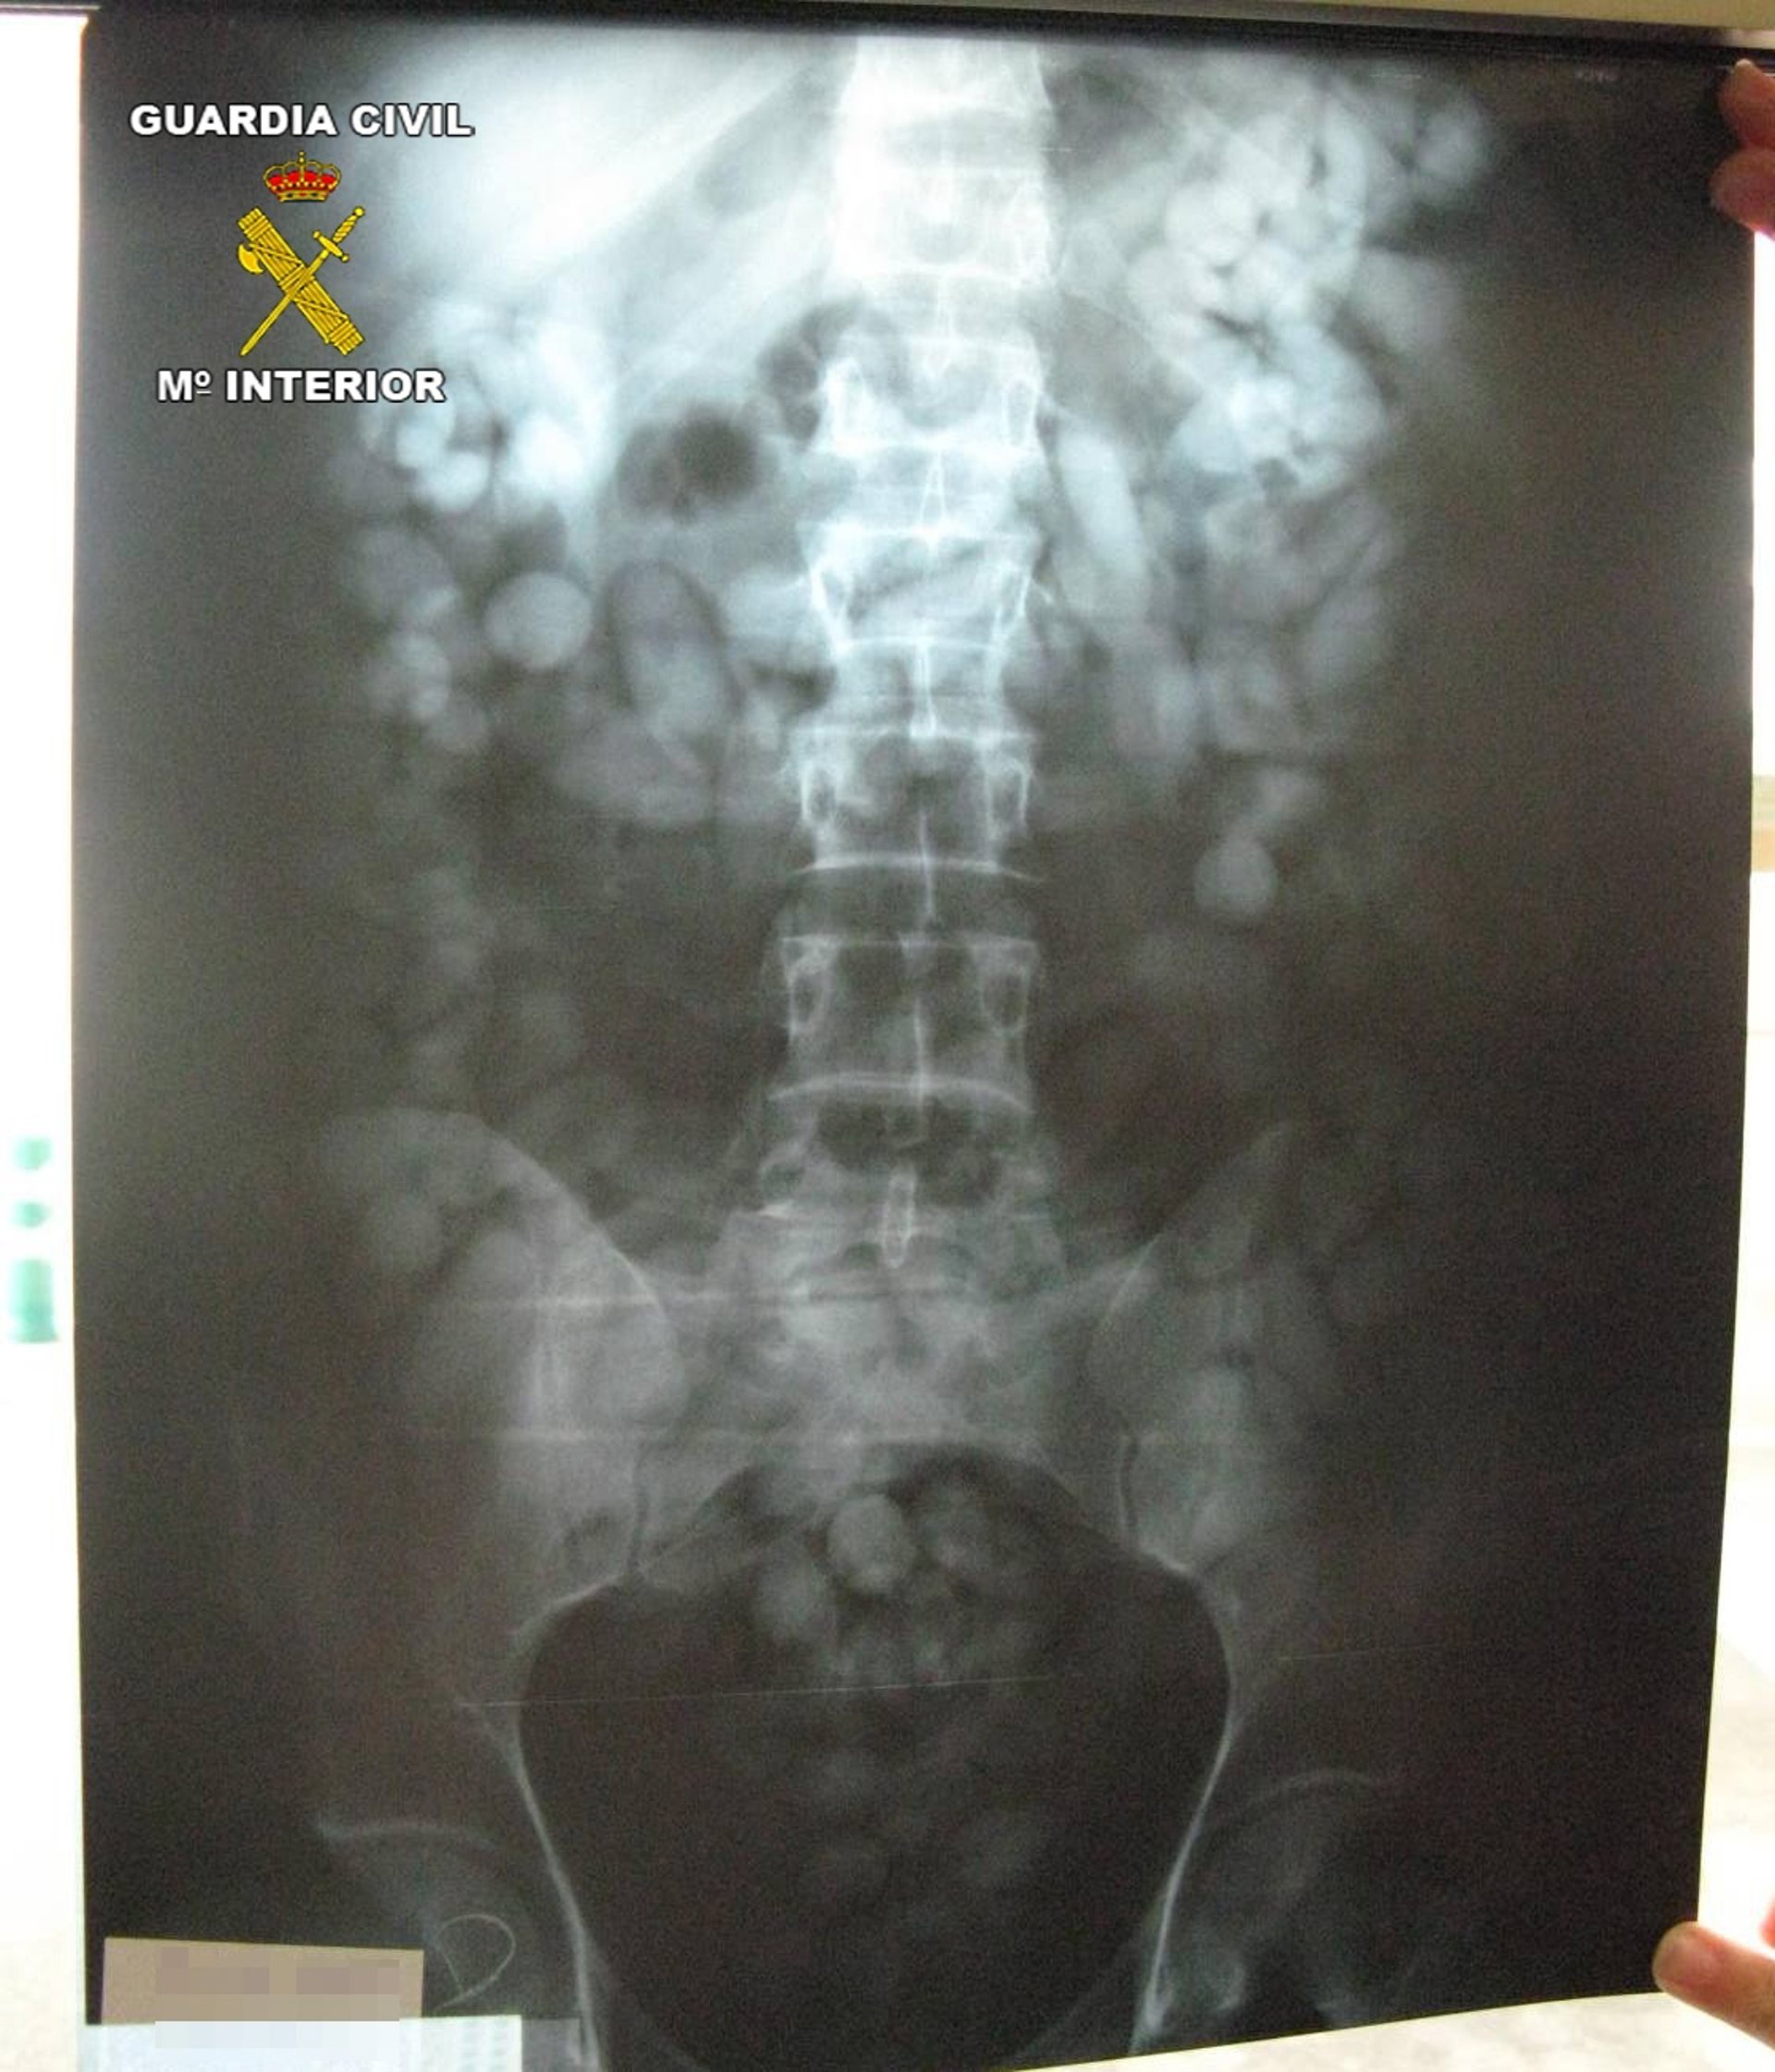

Durante la identificación, y después de invitarle a someterse a exploración radiológica voluntaria, los agentes detectan numerosos cuerpos extraños en el interior de su aparato digestivo, por lo que proceden a su detención como autor de un delito contra la salud pública. Durante los días posteriores a la detención practicada por los agentes de la Guardia Civil, el detenido ha expulsado 1044,33 gramos de hachís, distribuidos en 154 bellotas, que transportaba en el interior de su organismo.